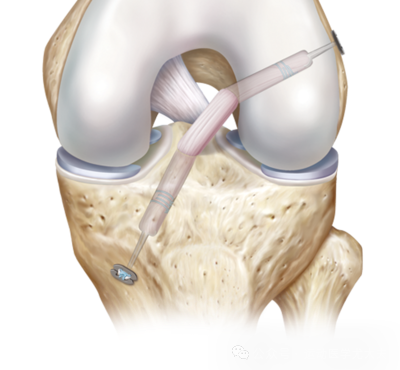

手术的原理图如上所示